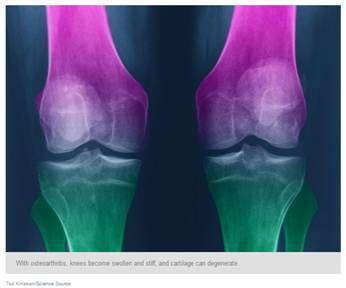

If you're among the estimated 27 million Americans who suffer from osteoarthritis of the knee or hip, then perhaps you've tried the nutritional supplements glucosamine and chondroitin. They've been marketed for joint health for about 20 years, and sales are still brisk. But do they help?

Glucosamine is an amino sugar that may help renew cartilage, and chondroitin sulfate is a complex carbohydrate that is thought to help cartilage retain water. Arthritis causes pain, swelling and stiffness in joints and damages cartilage over time. So the thought was maybe extra glucosamine and chondroitin could help maintain and even repair the damage.